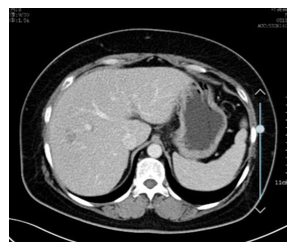

2018年11月5日,复查肝脏增强MRI(图3,4):肝脏多发结节灶,长T2长T1信号,DWI呈高信号,转移瘤考虑,其中右肝Ⅷ段包膜下及Ⅶ段腔静脉旁各见一T2高信号灶,大小分别约27 mm × 24 mm,11.5 mm × 9.8 mm;脂肪肝。

图3,4 2018年11月5日 第一次进展 肝脏增强MRI